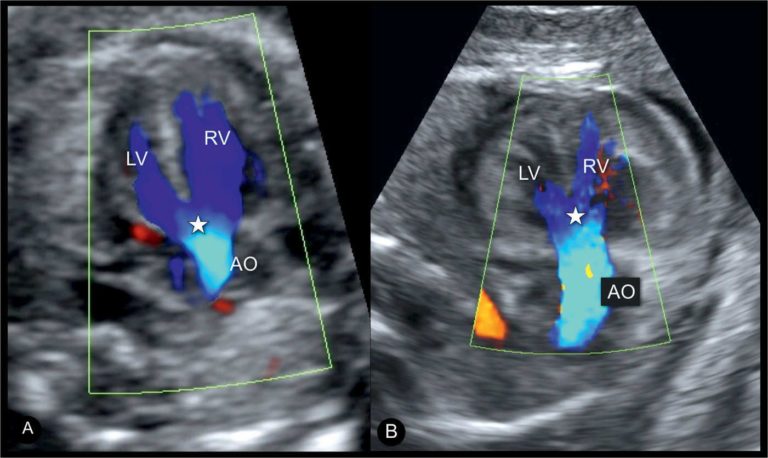

Ультразвуковое исследование сердца, или эхокардиография, – это неинвазивный метод диагностики, который позволяет визуализировать структуру и функцию сердца в режиме реального времени. Представьте себе, что это как «видео» вашего сердца, которое позволяет врачу увидеть, как оно бьется, как работают клапаны и насколько хорошо кровь циркулирует по сосудам. Это важный инструмент для выявления различных сердечных заболеваний, таких как пороки сердца, кардиомиопатия, ишемическая болезнь сердца и другие.

Традиционно, анализ изображений УЗИ сердца требует от врача высокой квалификации и большого опыта. Врач должен внимательно изучить каждый кадр, оценить размеры и форму сердца, скорость кровотока и другие параметры. Этот процесс может быть трудоемким и занимать много времени. Кроме того, существует риск субъективной ошибки, особенно в сложных случаях.

И вот тут на сцену выходит ИИ! Нейросети, обученные на огромном количестве изображений УЗИ сердца, способны анализировать данные с невероятной скоростью и точностью. Они могут выявлять даже самые незначительные отклонения от нормы, которые могут ускользнуть от внимания человеческого глаза. Представьте себе, что у вас есть ассистент, который никогда не устает, всегда внимателен и обладает энциклопедическими знаниями в области кардиологии. Именно таким помощником и является ИИ.

Представьте себе, что ИИ – это очень умный ученик, которого научили распознавать различные признаки сердечных заболеваний на изображениях УЗИ. Ему показали тысячи и тысячи снимков, на которых были изображены сердца с разными патологиями. ИИ научился отличать здоровое сердце от больного, определять размеры и форму сердца, оценивать скорость кровотока и выявлять другие важные параметры.

Когда вы приходите на УЗИ сердца, полученные изображения загружаются в программу, основанную на ИИ. Эта программа анализирует изображения и сравнивает их с теми, которые она видела раньше. Если программа обнаруживает какие-либо отклонения от нормы, она сообщает об этом врачу. Врач, в свою очередь, принимает решение о дальнейшем обследовании и лечении.